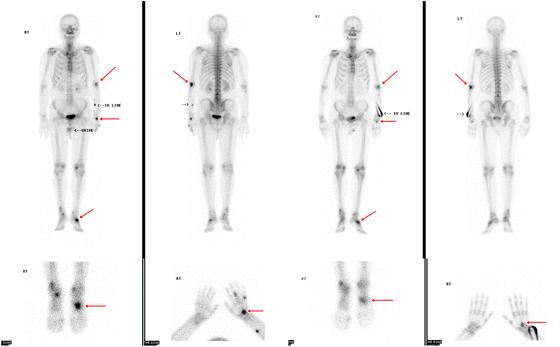

CT-scan of PET CT-scan

Deze test wordt gebruikt om te zien waar in het lichaam zich tumorcellen bevinden.

Een PET CT-scan is eigenlijk een combinatie van twee verschillende soorten scans, die worden “samengevoegd” om alles goed in beeld te brengen. PET staat voor “Positron Emission Tomography”.

Voor een PET-scan wordt gebruik gemaakt van fluorodeoxyglucose (FDG), een vorm van suiker met daaraan gekoppeld een licht radioactieve stof.

De meeste kankercellen hebben een verhoogde stofwisseling en verbruiken veel suiker. Door aan suikermoleculen een radioactieve stof te koppelen, kunnen kankercellen via een PET-scan zichtbaar worden gemaakt. (Met een PET-scan kan ook het ziektestadium worden bepaald, en kan worden nagegaan of de ziekte na een behandeling nog actief is).

4. Shawn Karls, Hina Shah, Heather Jacene, PET/CT for Lymphoma Post-therapy Response Assessment in Other Lymphomas, Response Assessment for Autologous Stem Cell Transplant, and Lymphoma Follow-up, Seminars in Nuclear Medicine, Volume 48, Issue 1, 2018, Pages 37-49, ISSN 0001-2998, https://doi.org/10.1053/j.semnuclmed.2017.09.004.

5. Park, Insook & Kang, Sungmin. (2017). Distal appendicular skeletal involvement of diffuse large B-cell lymphoma on technetium-99m methylenediphosphonate bone scintigraphy and 18F-fluorodeoxyglucose positron emission tomography/computed tomography: a case report. Journal of Medical Case Reports. 11. 10.1186/s13256-017-1246-y.